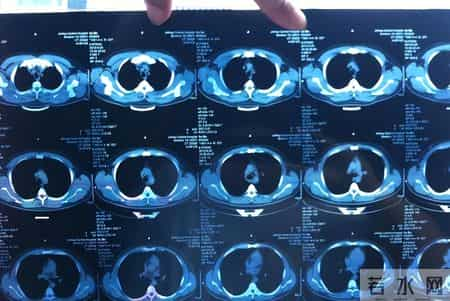

“一个健康人,怎么说倒就倒了?”这是急诊室里,家属最常说的一句话。一个60岁的叔叔,前一天还在厨房剁排骨,第二天一早却在厕所晕倒,CT显示:脑出血,30毫升,紧急手术。